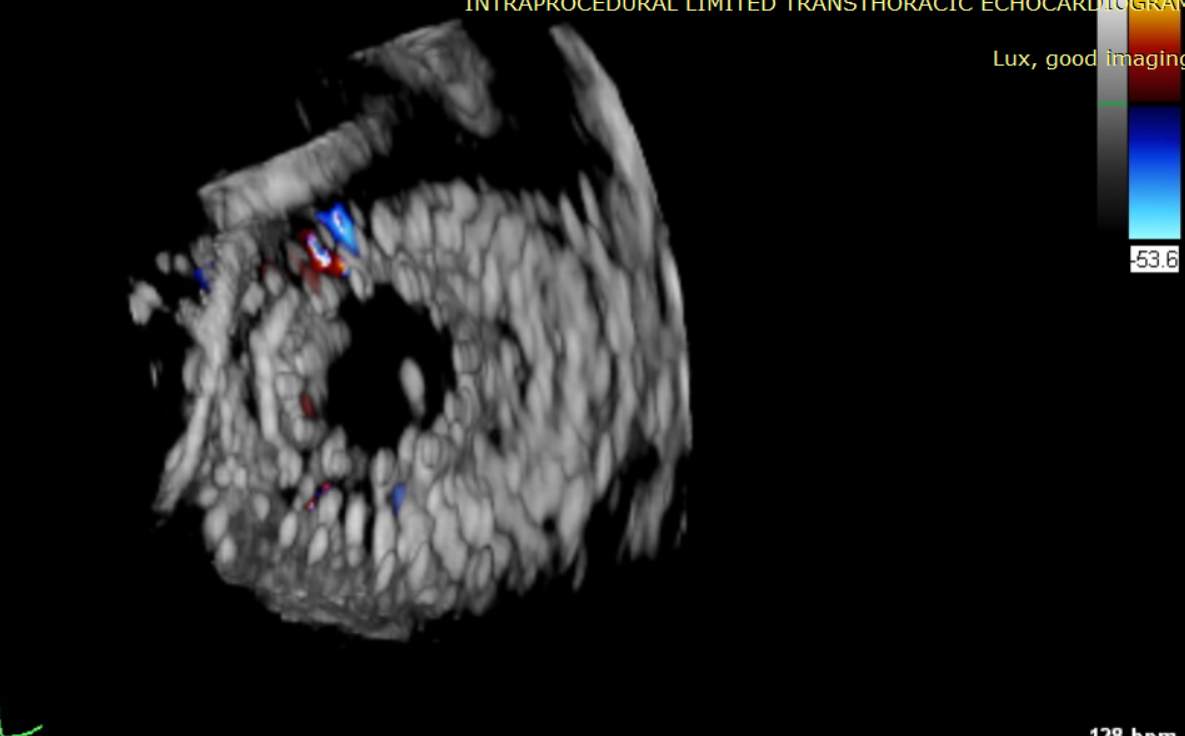

近日,美國紐約Montefiore醫(yī)學中心(Montrefiore Medical Center)的Azeem Latib教授團隊成功應(yīng)用LuX-Valve Plus經(jīng)血管三尖瓣置換系統(tǒng)為兩位三尖瓣大量反流的患者完成三尖瓣置換手術(shù)。術(shù)后超聲顯示人工三尖瓣植入穩(wěn)定,瓣葉啟閉良好,僅殘余微量瓣周漏?;颊哂谑中g(shù)室即刻拔除氣管插管,血流動力學改善顯著。此次手術(shù)是LuX-Valve Plus于紐約的首次臨床應(yīng)用,治療效果優(yōu)異。

經(jīng)過Azeem Latib教授帶領(lǐng)的多學科團隊討論,本次接受治療的兩位患者均為外科手術(shù)高危;且受限于影像和解剖結(jié)構(gòu)的局限性,其他的經(jīng)導(dǎo)管修復(fù)、置換系統(tǒng)均不適用。而LuX-Valve Plus獨特的錨定機制(即脫離徑向支撐力的“室間隔錨定”設(shè)計理念)和對術(shù)中超聲影像的低要求,使得Azeem Latib教授團隊認為這一中國創(chuàng)新醫(yī)療器械可以對這兩名患者進行有效治療。